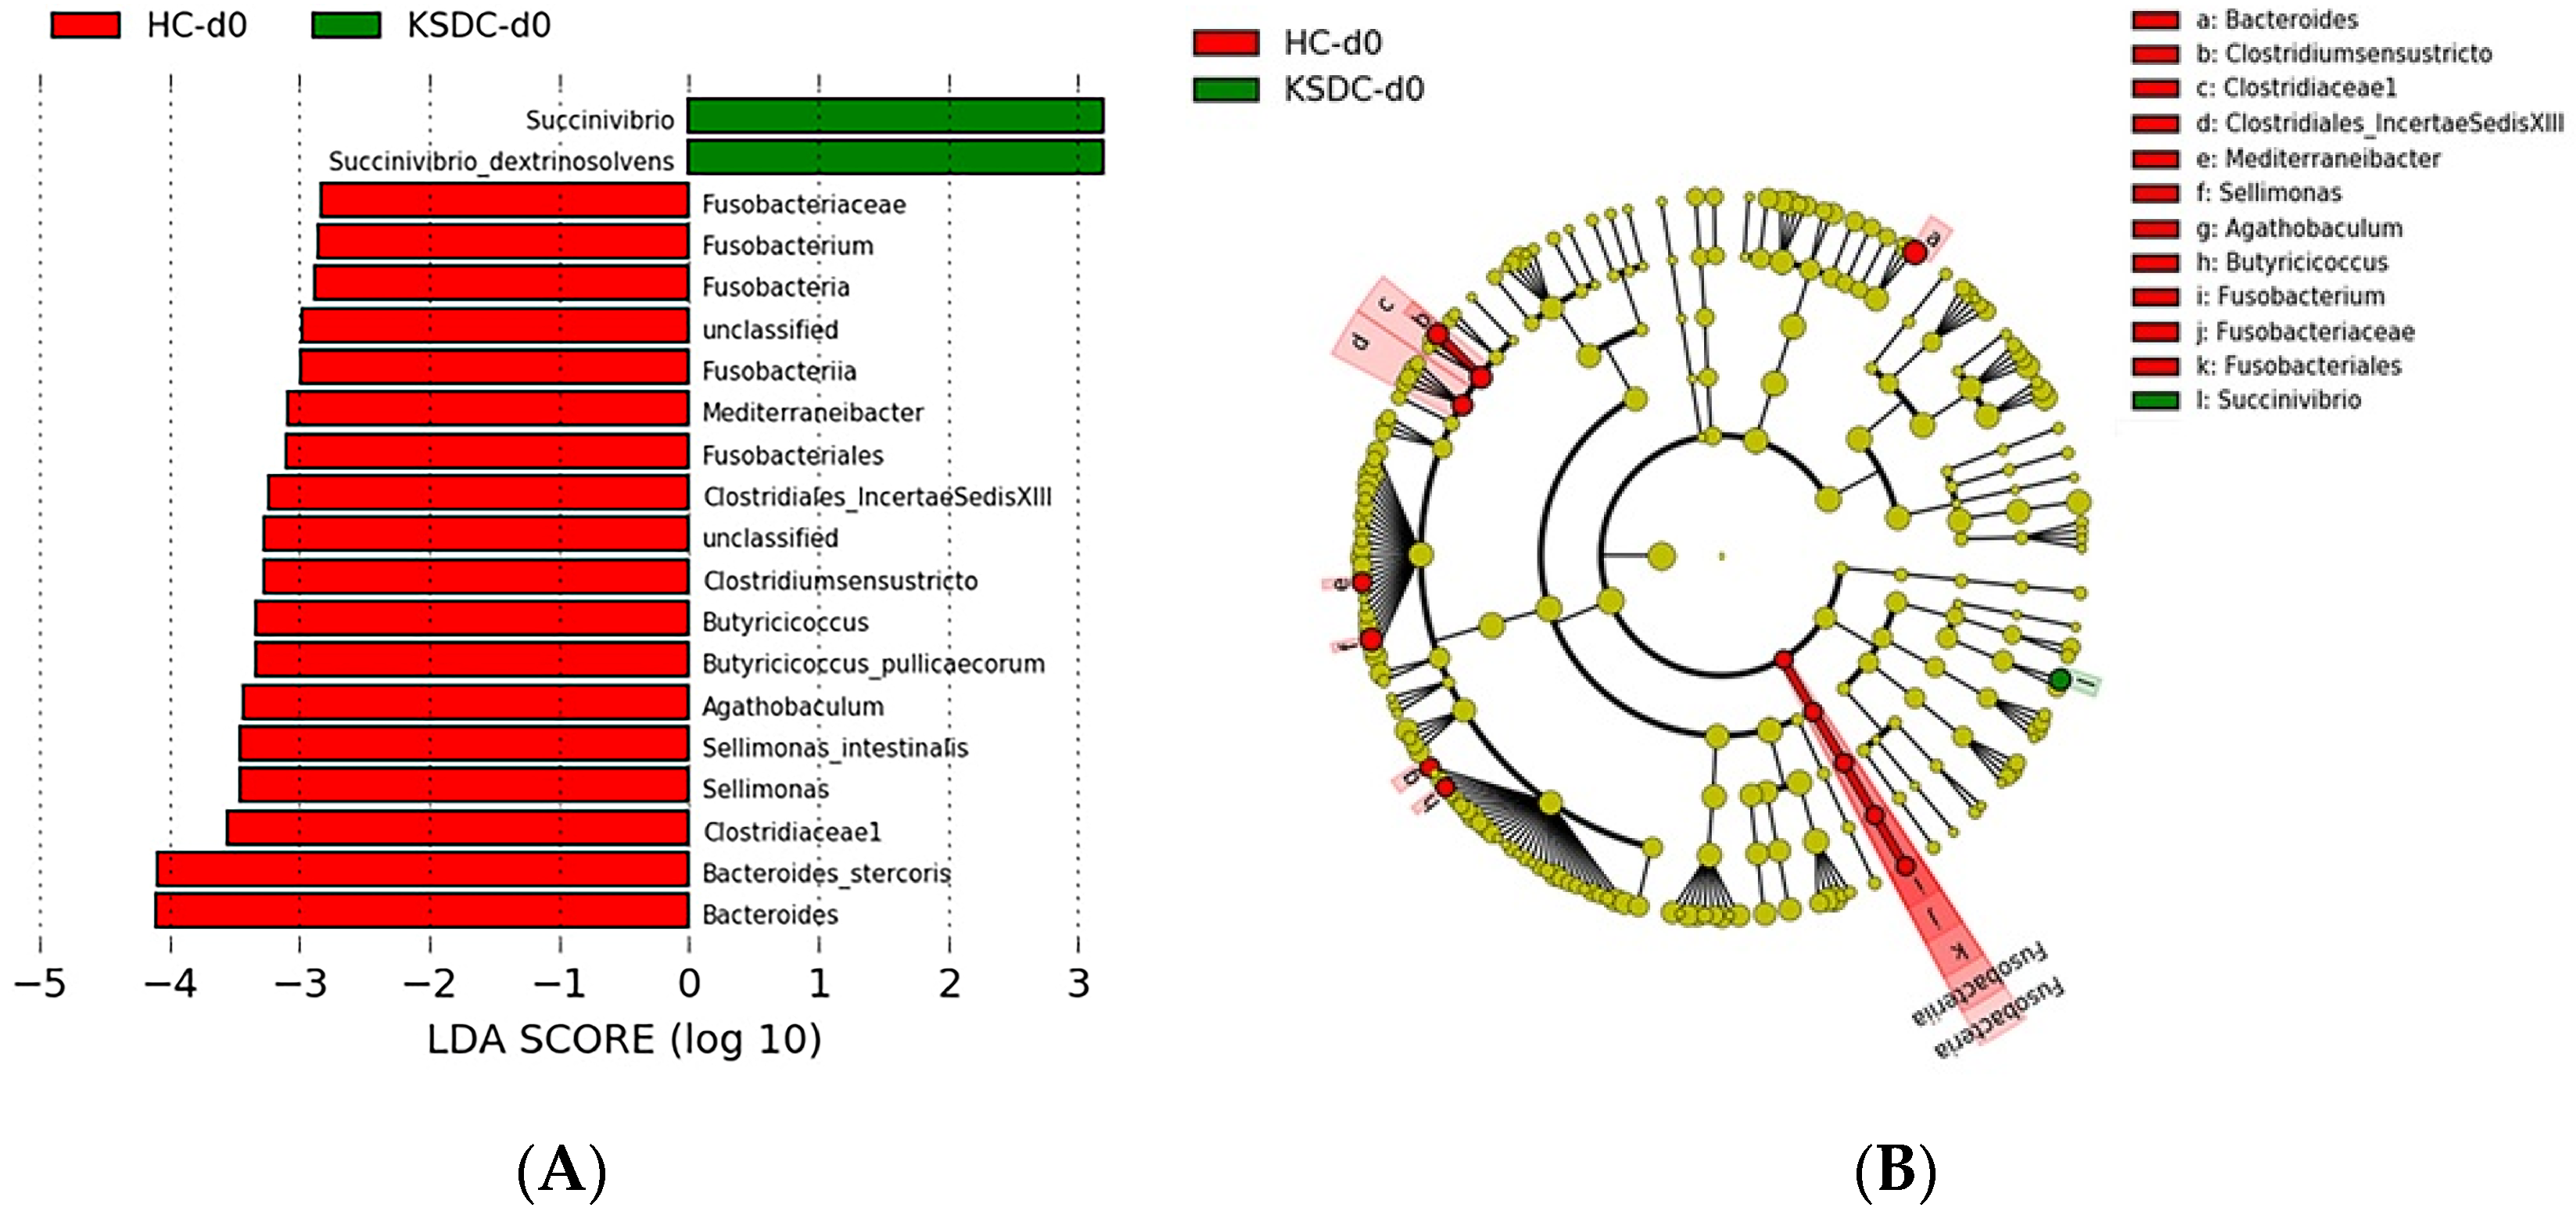

Taxonomic Analysis of the Intestinal Microbiota Composition at D0 in the Two Cat Populations

Biodiversity of the Fecal Microbiota in the Two Cat Populations